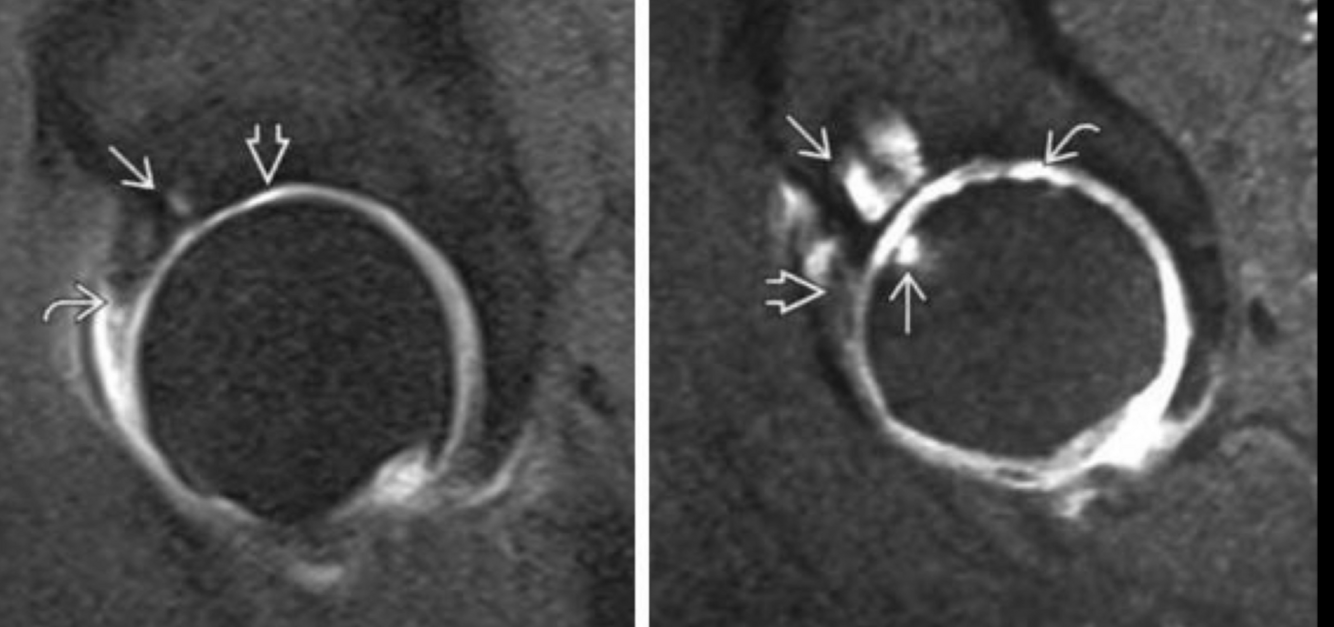

RM PZFAC

A

LOMEJOR

Permite ver edema óseo

pinzamiento leve

quistes

lesión de labrum